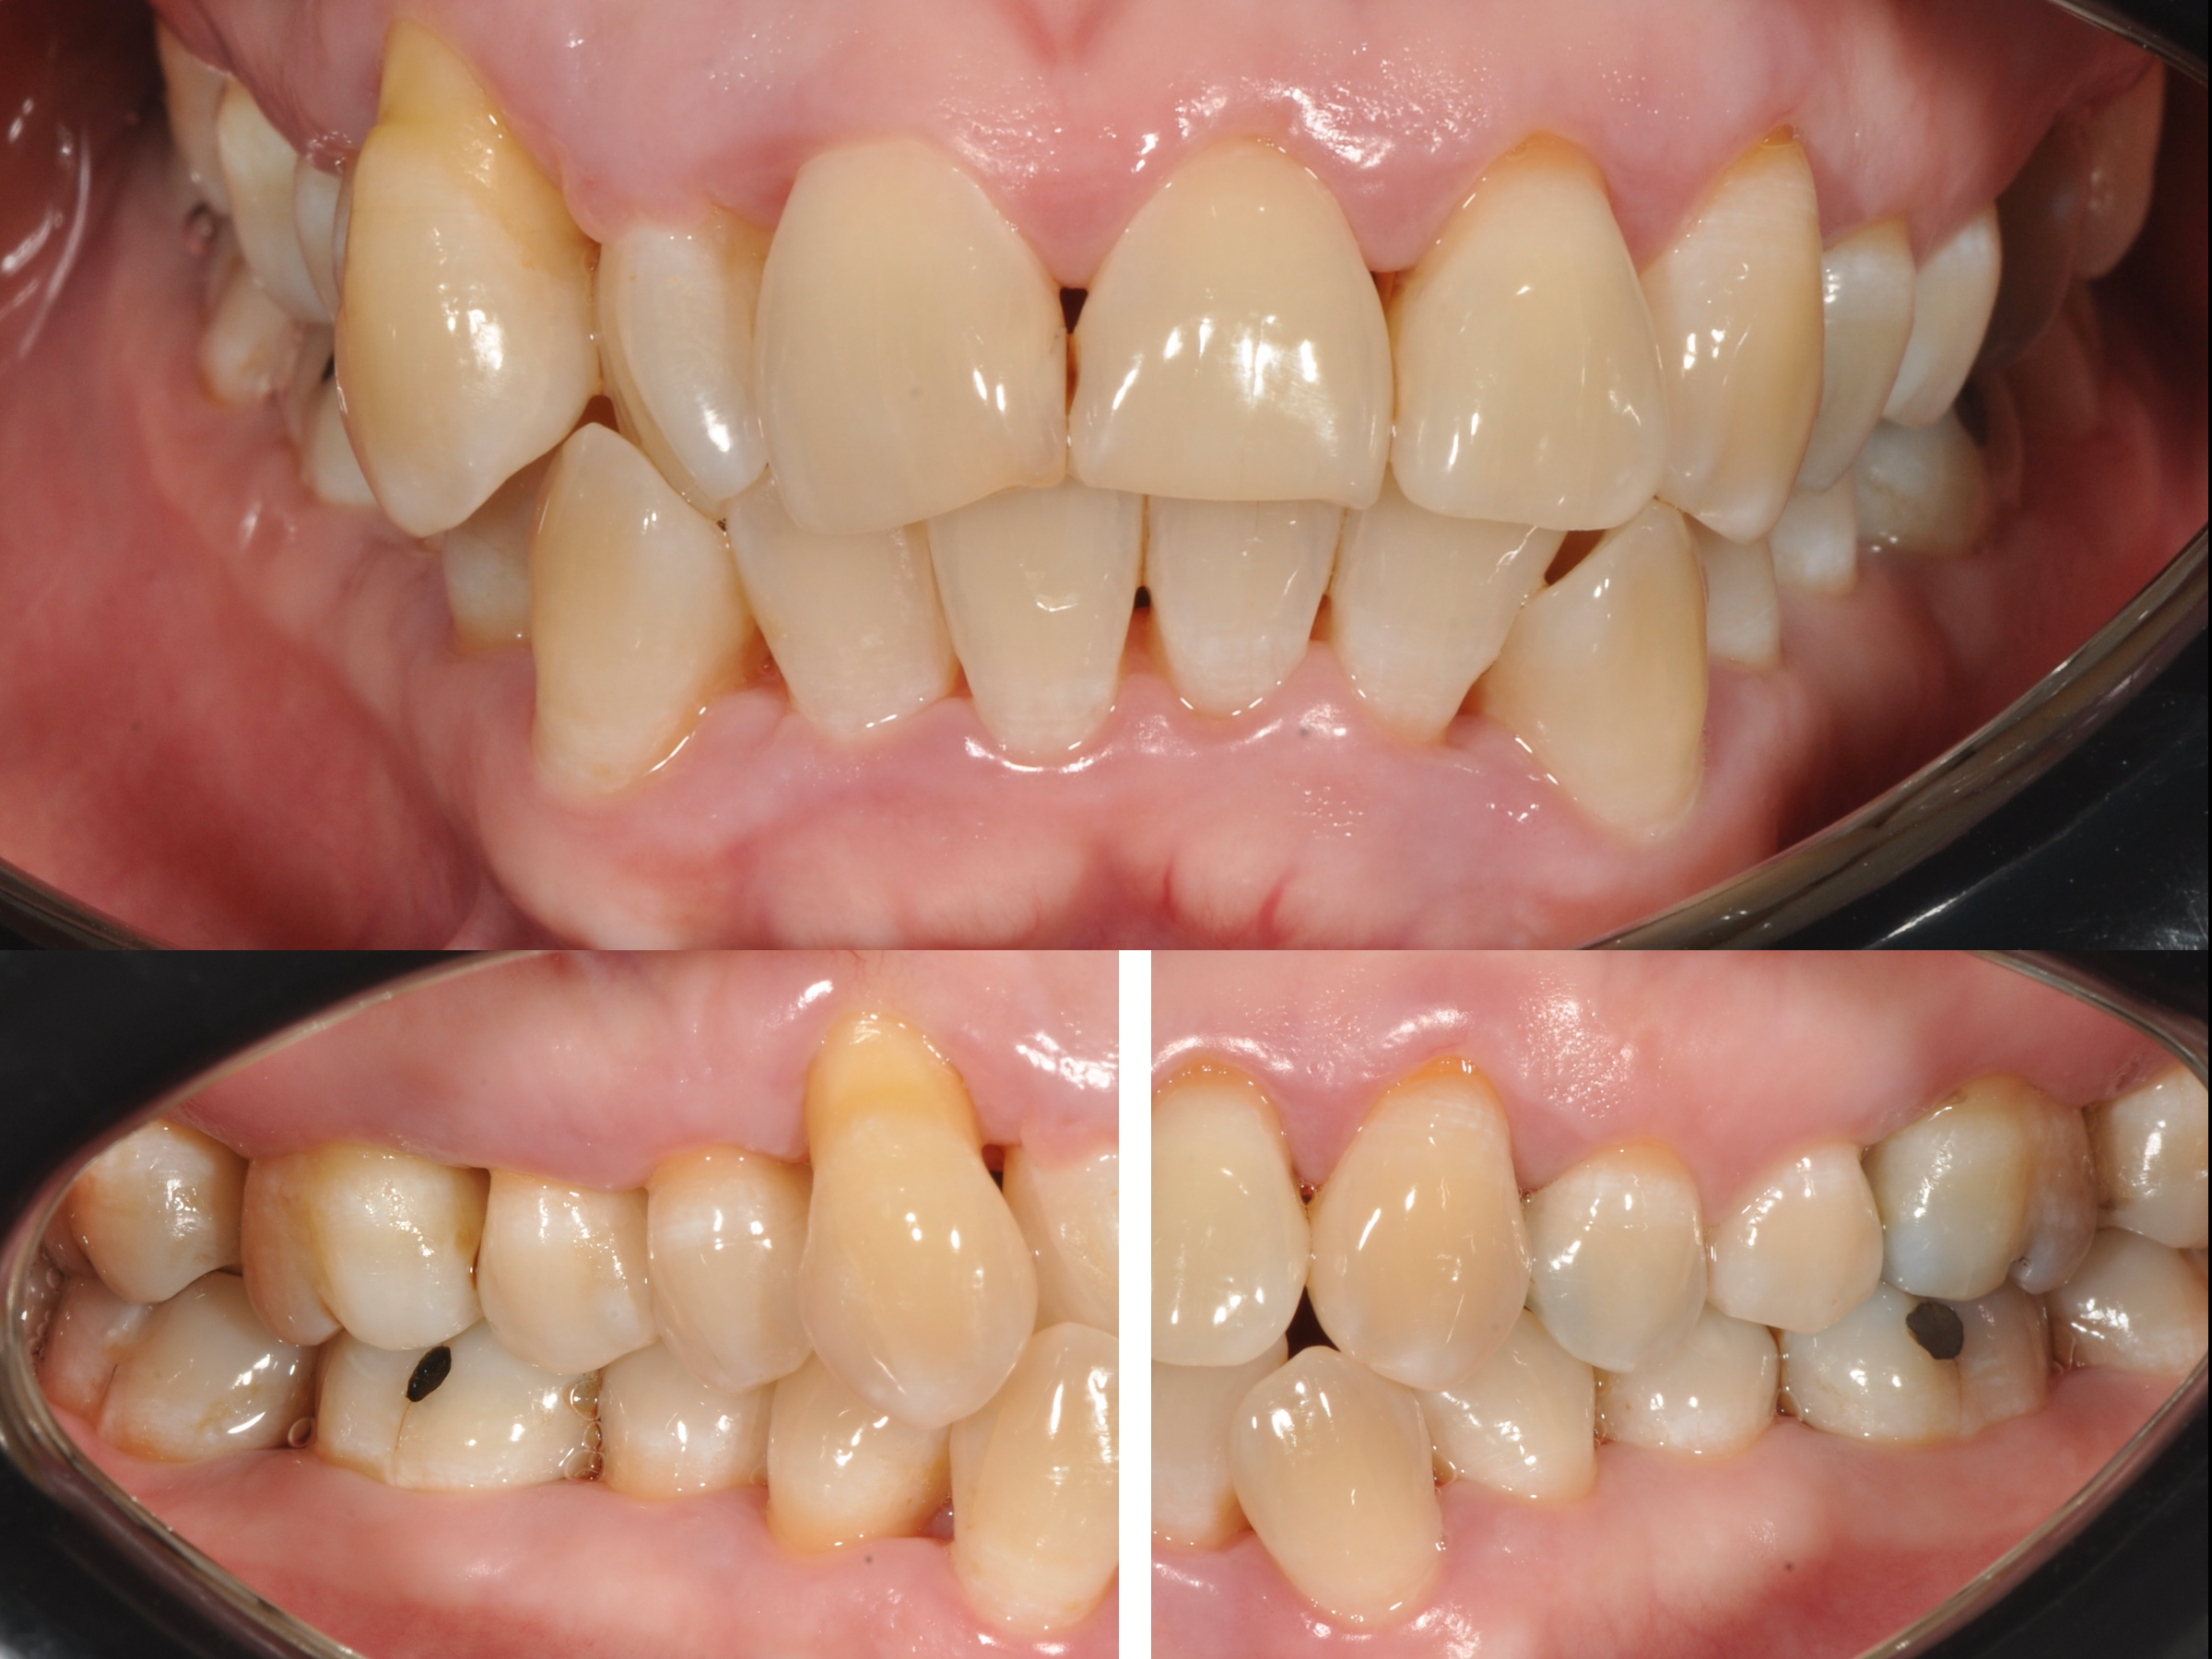

Le immagini cliniche del prima e dopo trattamento e il test di placca al 100% che accompagnano questo articolo mostrano visivamente quanto sia determinante il controllo del biofilm nella guarigione dei tessuti.

L’inquadramento diagnostico: status radiografico e sondaggio parodontale (foto in calce)

Prima e dopo: cosa dimostrano le immagini

Le fotografie cliniche allegate mostrano:

• Gengive infiammate e sanguinanti prima della terapia

• Riduzione dell’edema e dell’eritema dopo la decontaminazione

• Miglioramento della salute gengivale senza incisioni chirurgiche

L’immagine del test di placca al 100% è particolarmente significativa: quando tutto è colorato, significa che il biofilm è ovunque. È da lì che bisogna partire.